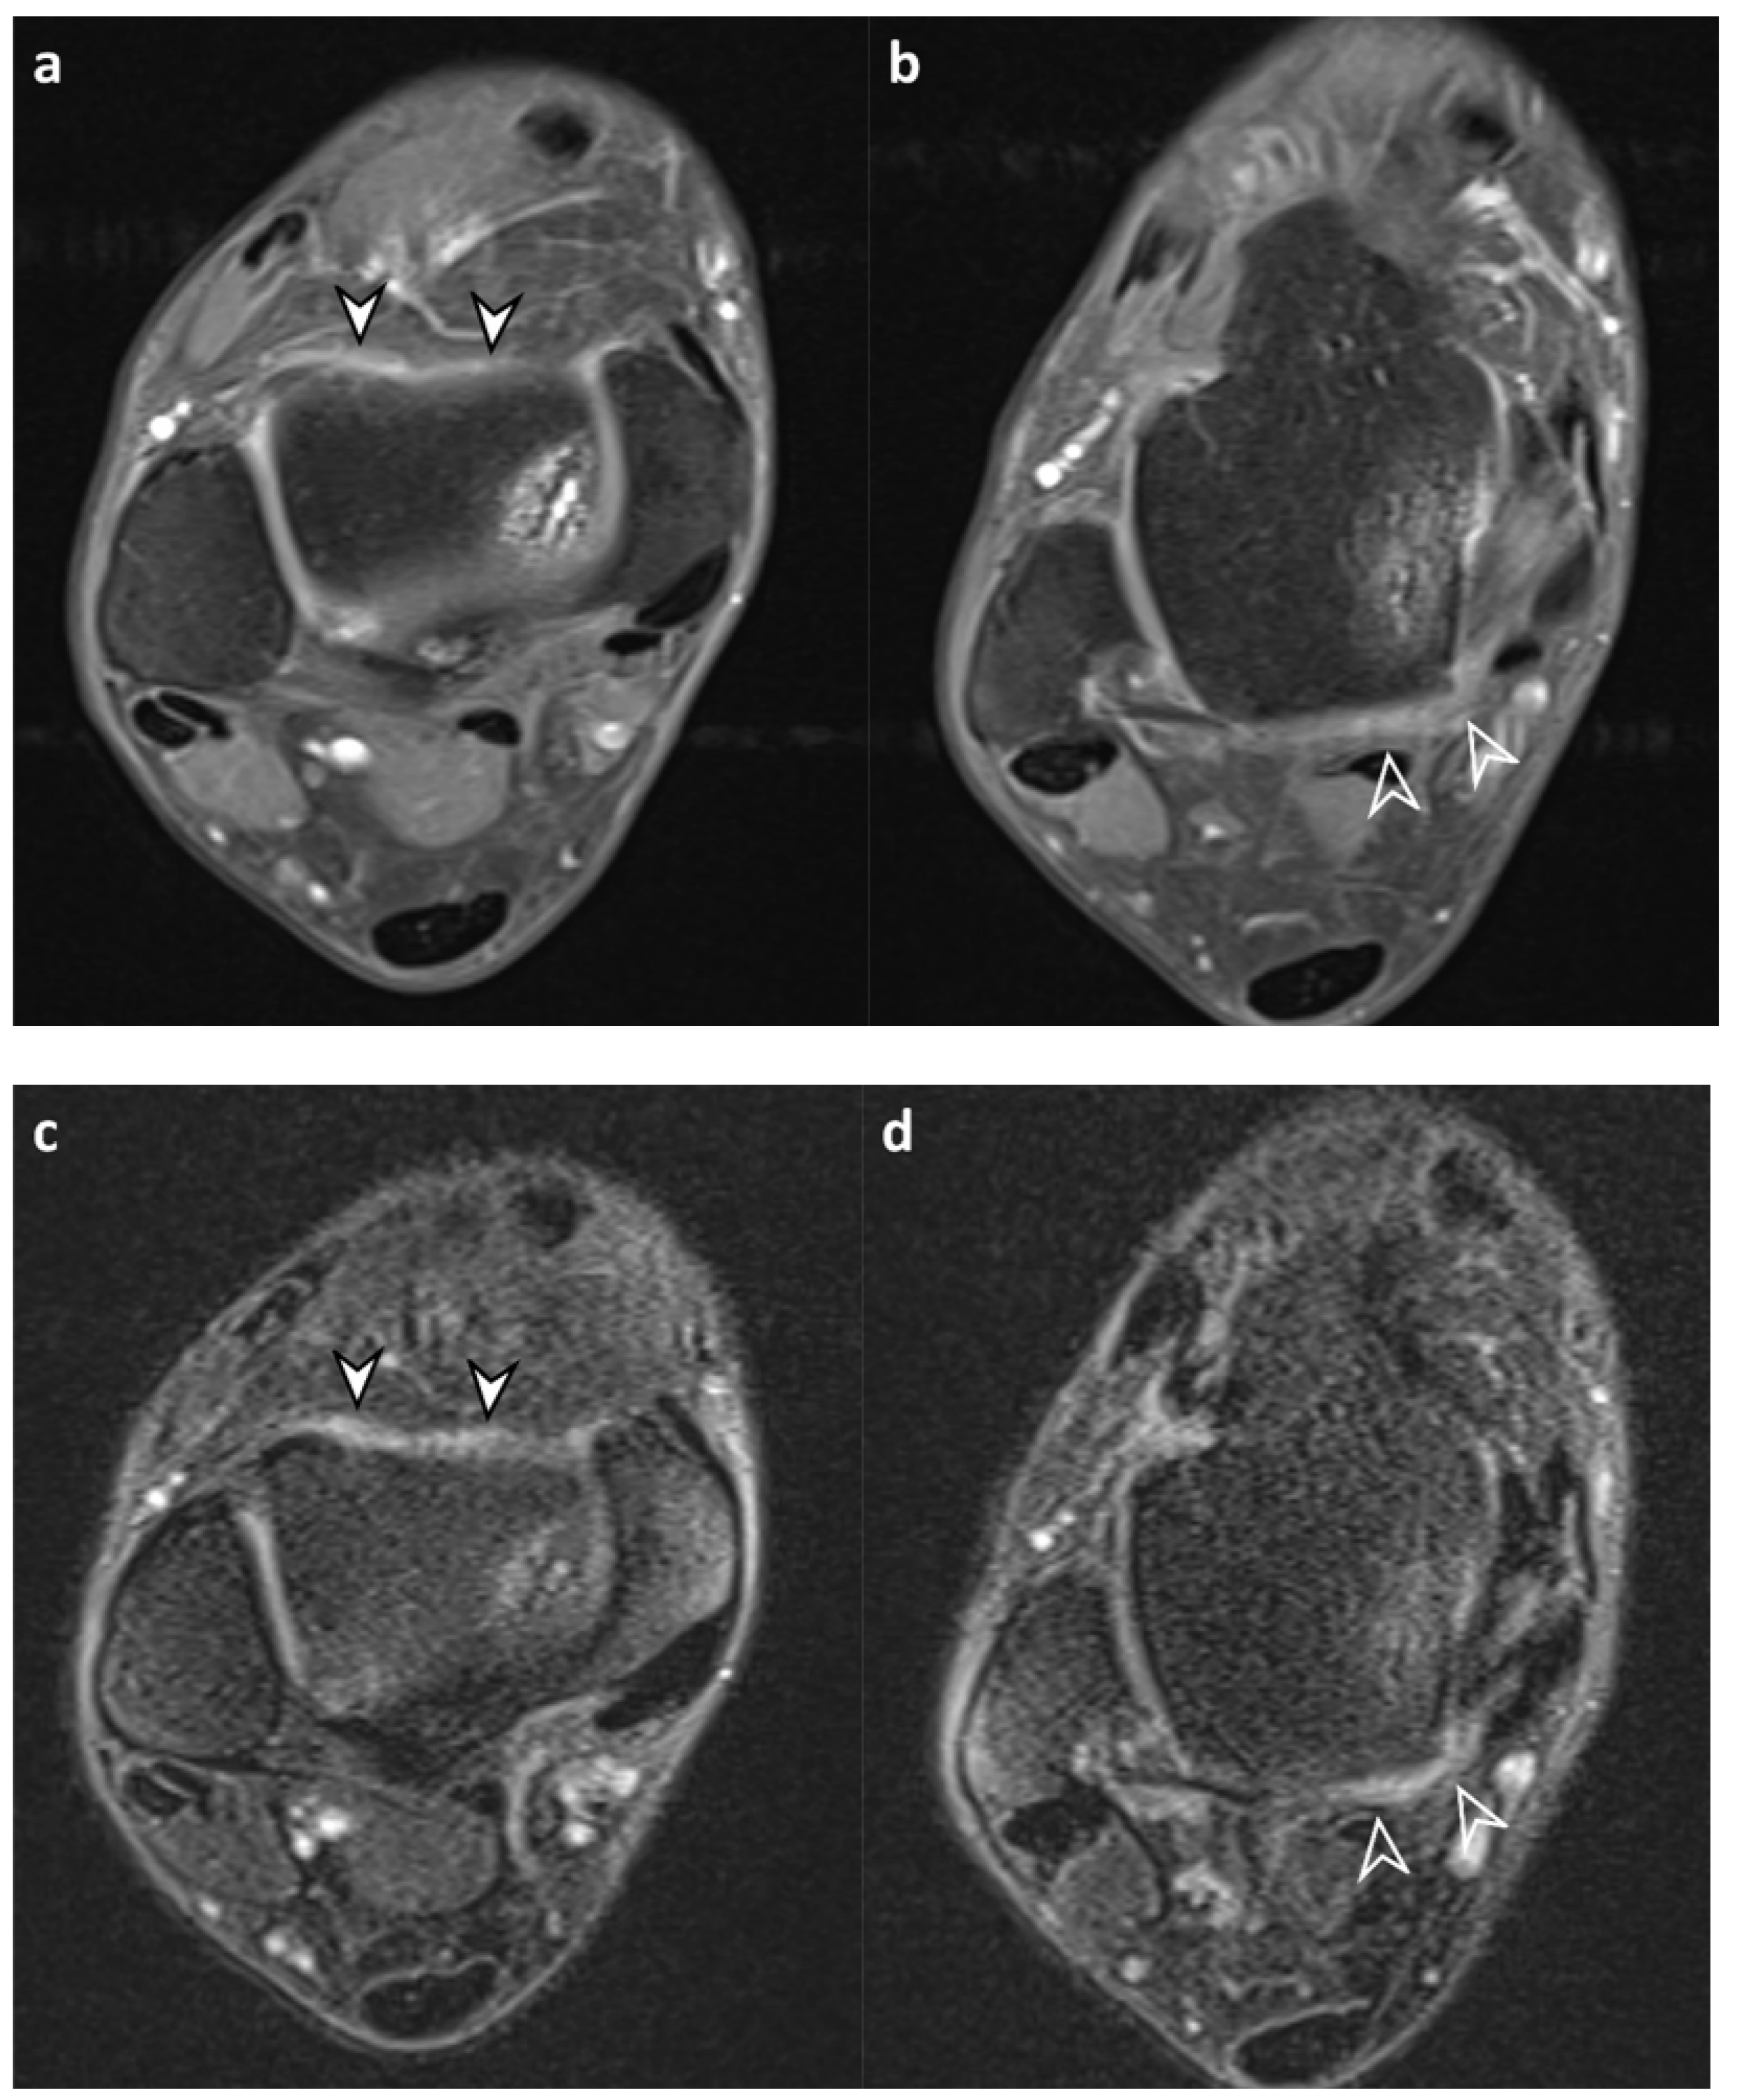

3.2. Synovial Visibility on FLAIR-FS and CE-T1 Images